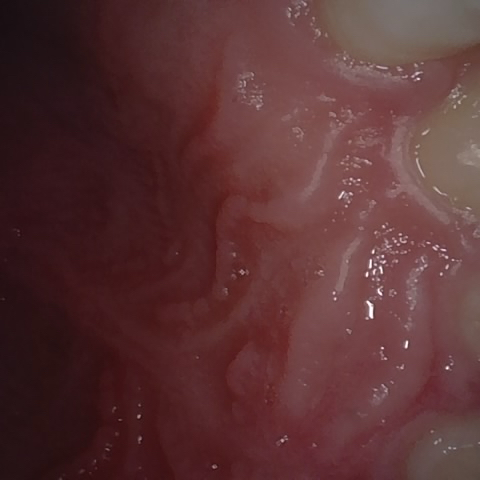

NHD39990

Annotated as "Good"

Original Image Rendering Image